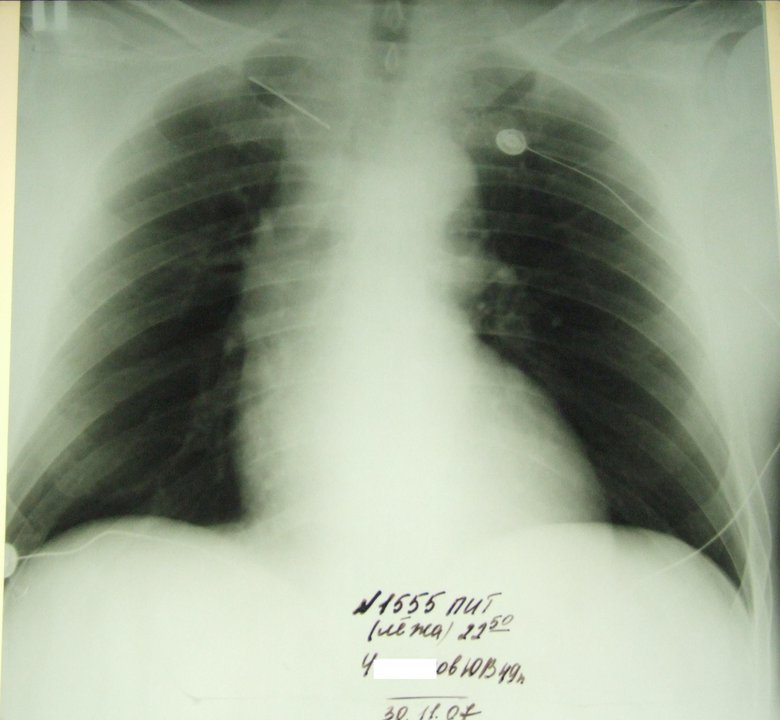

Интубационная трубка на карине, аж согнулась

Обсуждалось здесь